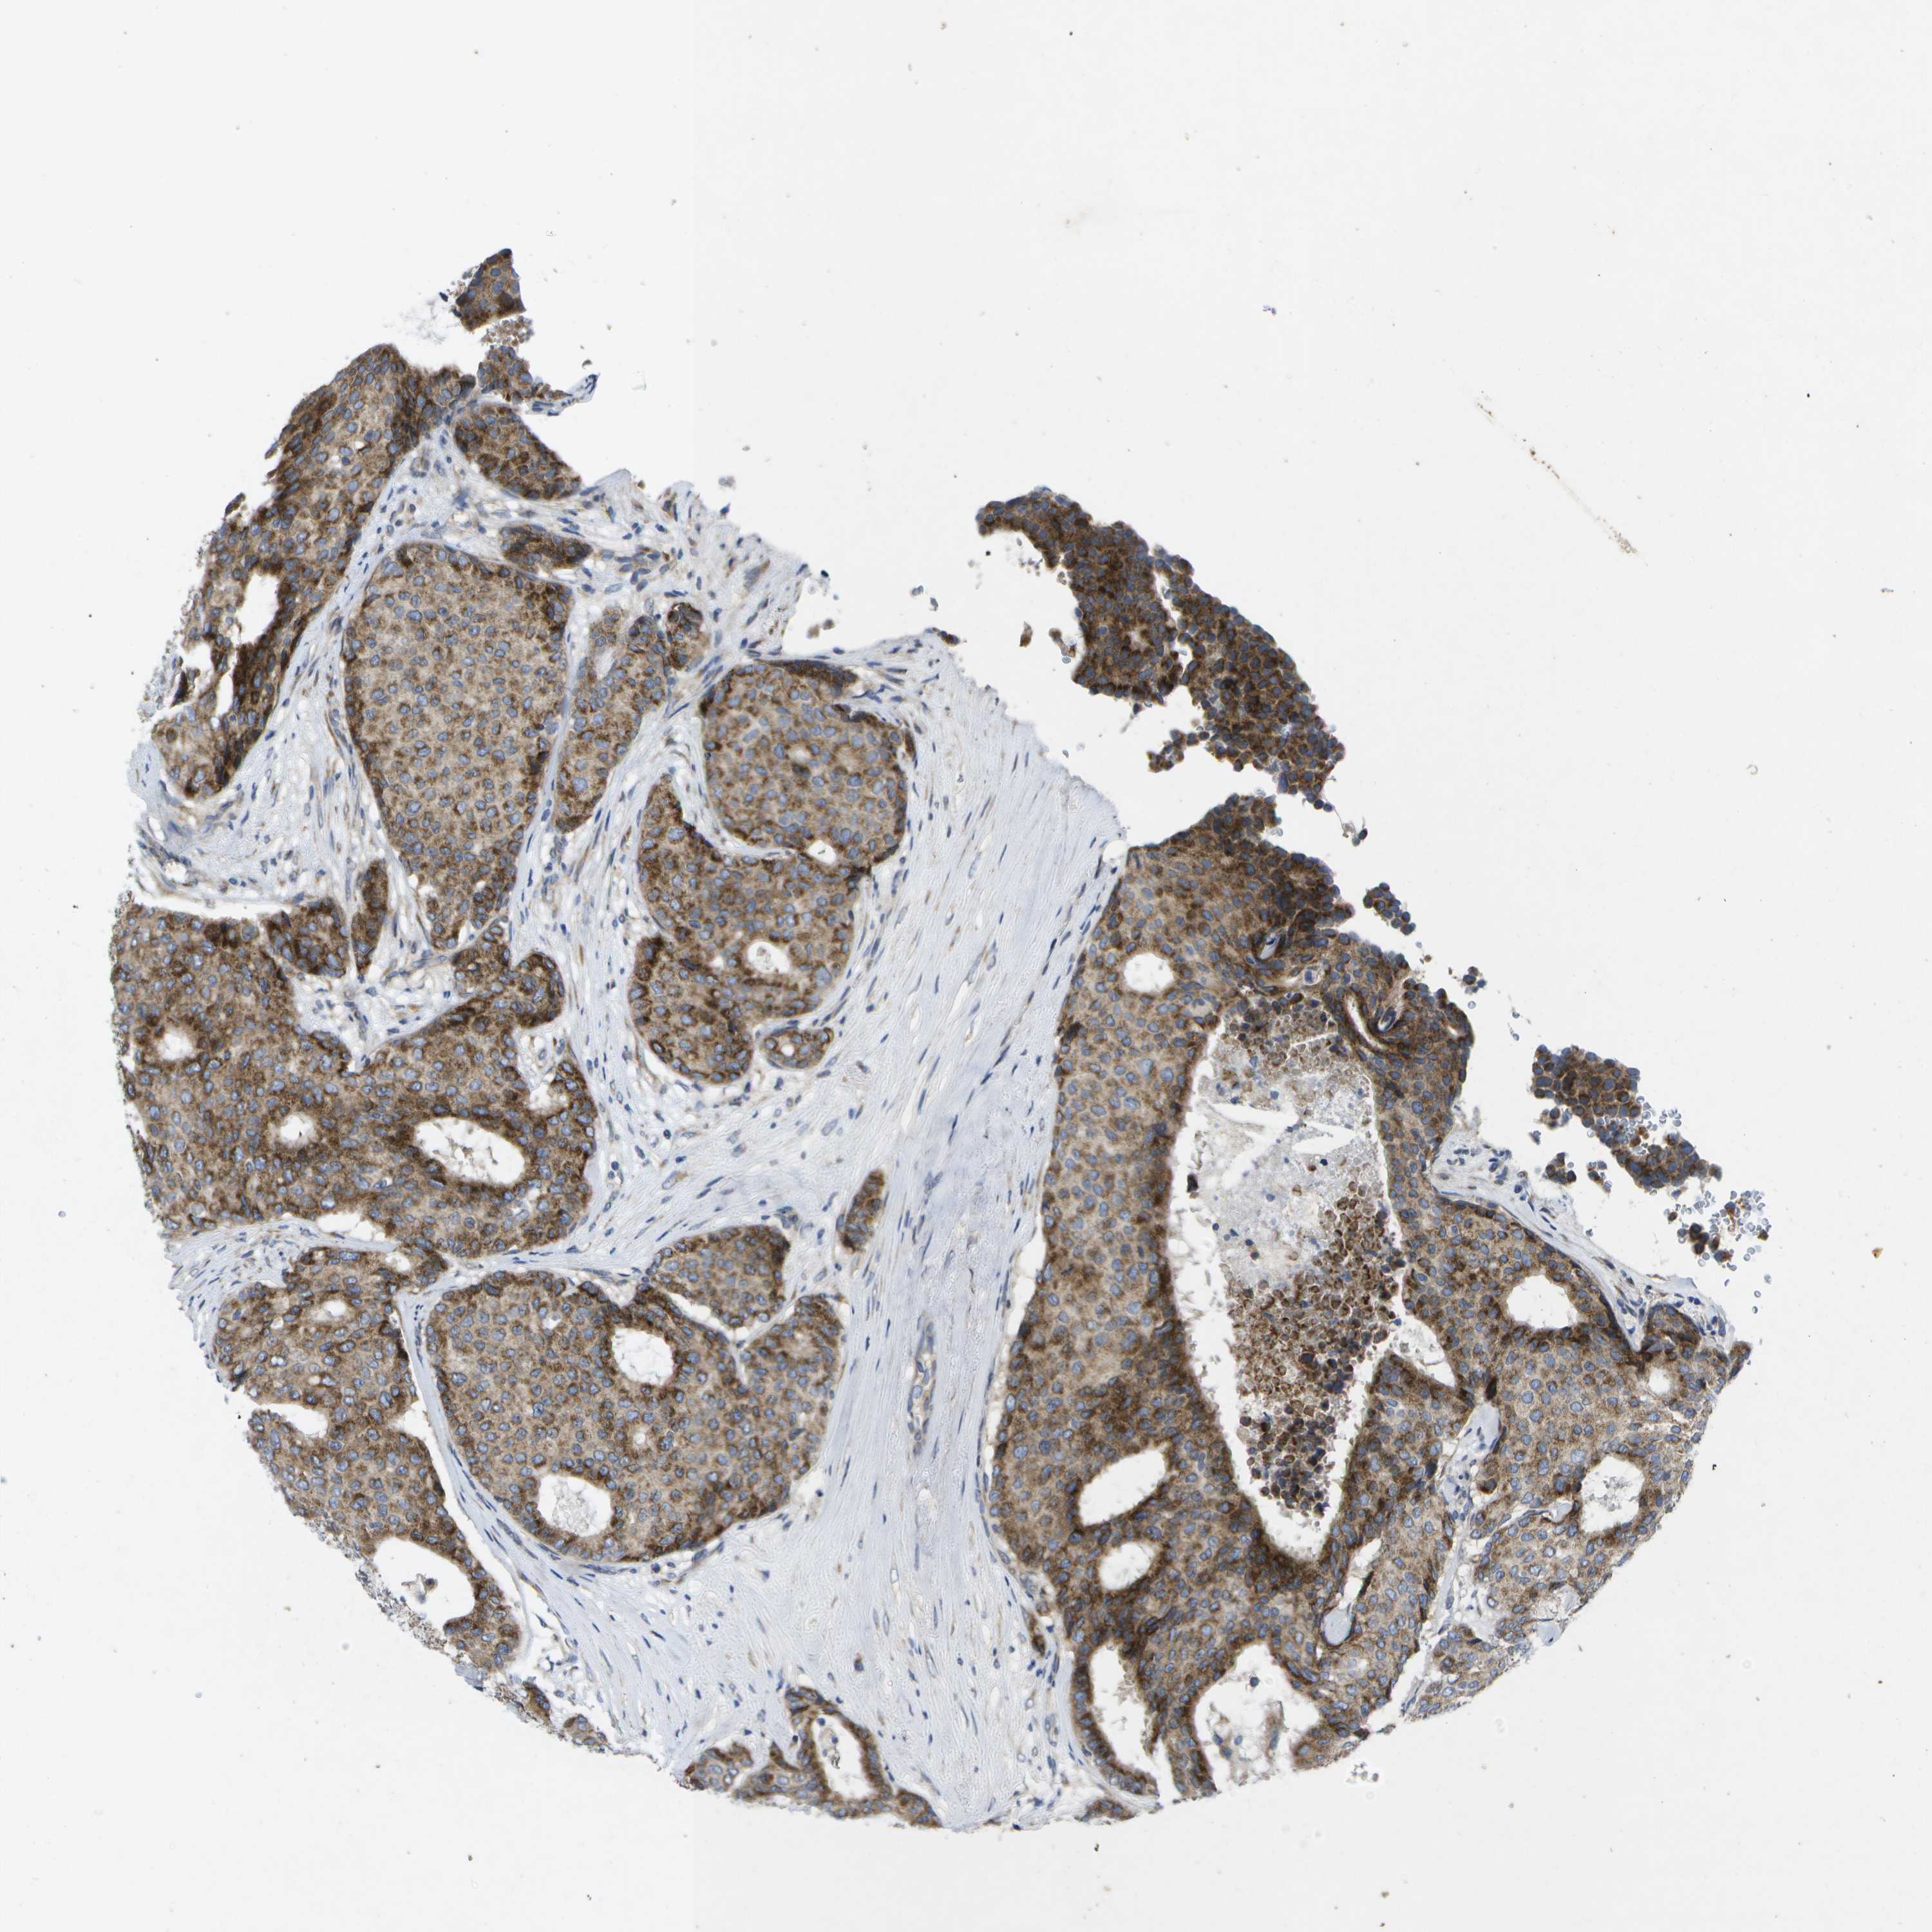

BRCA TCGA BRCA VALIDATION PROTEIN EXPRESSION